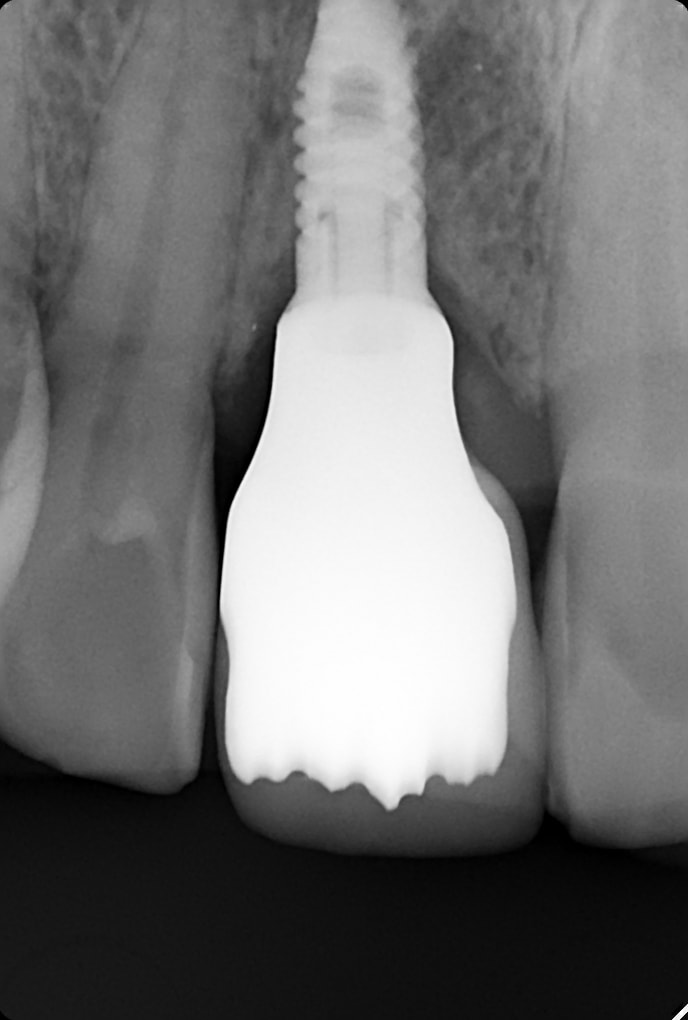

Bonjour ce patient se plaint de douleurs intermittentes par période gencive au dessus de l implant

pano 2021 2023

Par contre on dirait quand même une jolie poche autour de l'implant, surtout en distal quand on compare avec ce qu'on peut distinguer de la 1ère pano.

Ca ressemble plus à une péri-implantite (mucosite me diraient surement les puristes, quoi que je suspecte une vraie perte osseuse) qu'autre chose.

a mon sens: peu d'osteointégration. et peut être un poil pres de la dent d' acoté.

Peut-être une rapport ancrage/couronne clinique peu favorable, qui dans certaines situations entraine une surcharge passagère au niveau de l'implant...

ton avis sur l implant lui même moi je vois pas de soucis osteointegration ou peri implantite ?

C'est une couronne zircone sur une T-Base ?